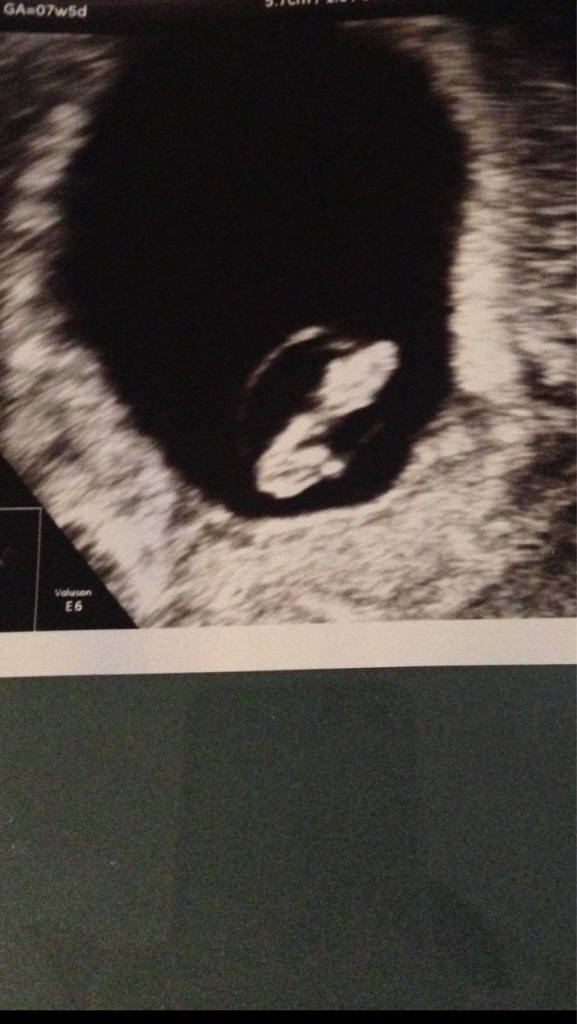

Witaj to u mnie na odwrot 38 latek corka 8 mscy i teraz 8 Tydz z tym ze corka dlugie lata staran i ivf a Teraz szok naturalnie

Dzus slyszalam serduszko i wierze ze bedzue dobrze

1510850560-cdea065ef19c9142-aaaaaa.jpeg

Napisane na iPhone w aplikacji Forum BabyBoom